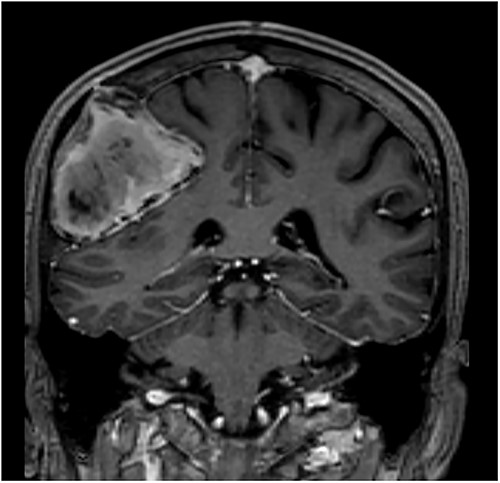

Our patient is a 76-year-old gentleman with medical history of hypertension and lumbar spondylosis. He did not have any previous history of trauma or systemic infections. He had presented to his local hospital with a 2-day history of left arm numbness. He did not report any headaches or giddiness. On clinical assessment, he did not have any neurological deficits. A CT brain and MRI brain (Figs 1–5) with contrast revealed a 53 × 53 × 41 mm partially calcified, heterogeneously enhancing conical shaped right extra-axial parietal convexity lesion. The overlying calvarial bone was remodelled and possibly eroded. There was evidence of prior haemorrhage within the lesion and scattered internal and peripheral calcification. Based on these characteristics, the possible diagnoses were that of an intraosseous meningioma, haemangioma and giant cell tumour. Patient was consented for craniotomy and excision of the tumour.

T1-weighted contrast-enhanced coronal MRI scan showing the lesion with intralesional haemorrhagic products. There is no evidence of dural invasion.